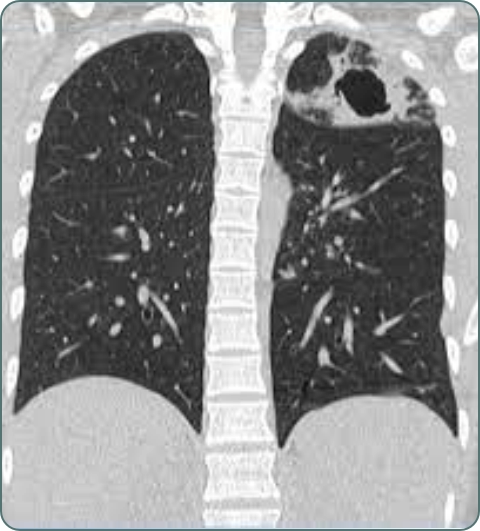

CT Scan Chest

Detailed cross-sectional imaging of chest for complex conditions. High-resolution CT for interstitial lung disease and lung cancer screening.